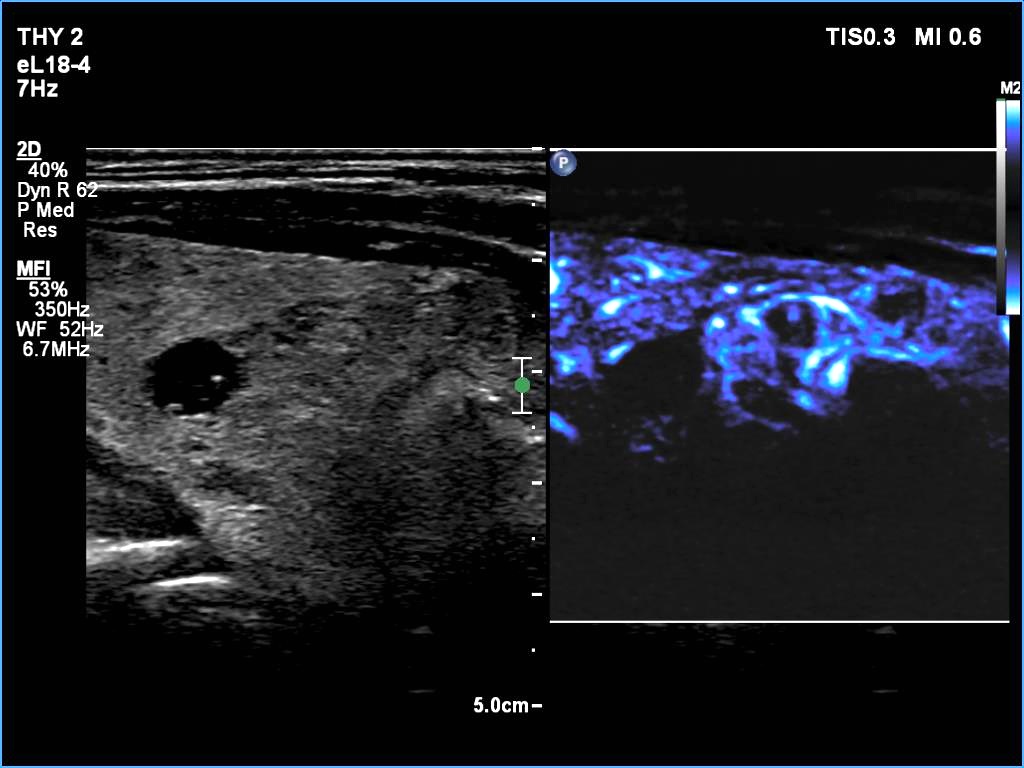

The composition of the nodule - case 2180 (ultrasonographic picture 10)

Left lobe, longitudinal scan, microflow imaging. There is a vessel in the ventral part of the cystic lesion while the lower nodule has vessels both at the periphery and in its central portions.